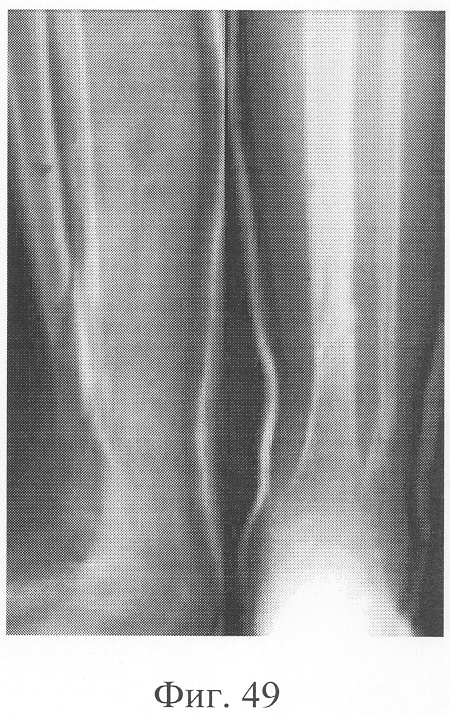

Больной П., 46 лет, поступил для планового оперативного лечения с диагнозом «ложный сустав левой большеберцовой кости» (фиг.47-49 – клинические и рентгенологические данные до операции). В анамнезе открытый перелом обеих костей голени, по поводу которого после проведения первичной хирургической обработки раны был наложен аппарат внешней фиксации с одномоментной репозицией. В связи с замедленной консолидацией проводилась микрокомпрессия и микродистракция, что не имело четкого положительного эффекта. Через 11 месяцев после травмы отмечалась выраженная патологическая подвижность при клинической пробе, рентгенологически отмечены признаки формирования ложного сустава. Аппарат внешней фиксации был демонтирован, и после заживления ран выполнена операция: экономная резекция костных фрагментов, фиксация в аппарате, костная пластика деминерализованным костным трансплантатом, заселенным аутологичными мезенхимальными стволовыми клетками по предложенной методике. В послеоперационном периоде дренажи удалены на 2-е сутки, швы сняты на 14 сутки, с 5-х суток разрешена ходьба при помощи костылей, с 7-х суток нагрузка на оперированную конечность (фиг.50-52 – клинические и рентгенологические данные в процессе лечения). Аппарат внешней фиксации демонтирован через 3 месяца при клинико-рентгенологической картине сращения (фиг.53-55 – результат лечения).